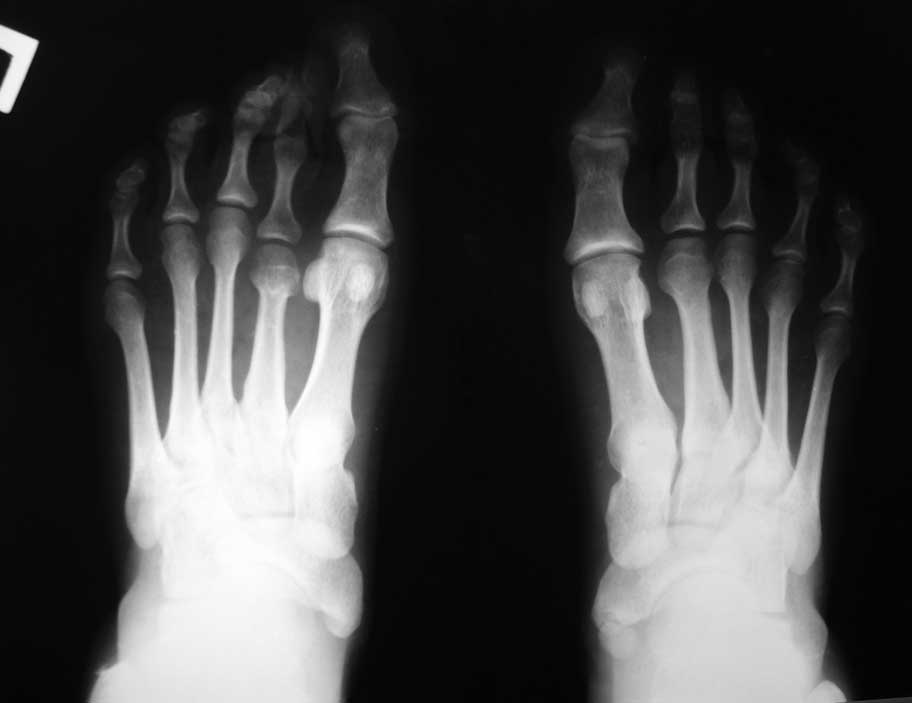

Палец приподнят над остальными за счет избыточного тыльного сгибания в плюснефаланговом суставе. Если уж думать о резекции, то о резекции основания основной фаланги, а не головки. Иначе основная фаланга так и останется приподнятой, а палец как мешал, так и будет мешать. Только станет короче и тугоподвижнее за счет фиксации спицей. После подобной операции палец вполне можно эффективно удерживать в нужном положении повязкой. А при необходимости положение пальца во время перевязки можно легко подкорректировать. Во вложенном файле пример возможности удержания пальцев повязкой в гораздо более серьезной ситуации.

Здесь стопа до и через неделю после вмешательства на первой перевязке. На операции были выполнены субкапитальные остеотомии 2-4 плюсневых костей, оснований основных фаланг 2-5 пальцев и средних фаланг 2-3 пальцев. И даже при таком объеме нужды в фиксации спицами нет.